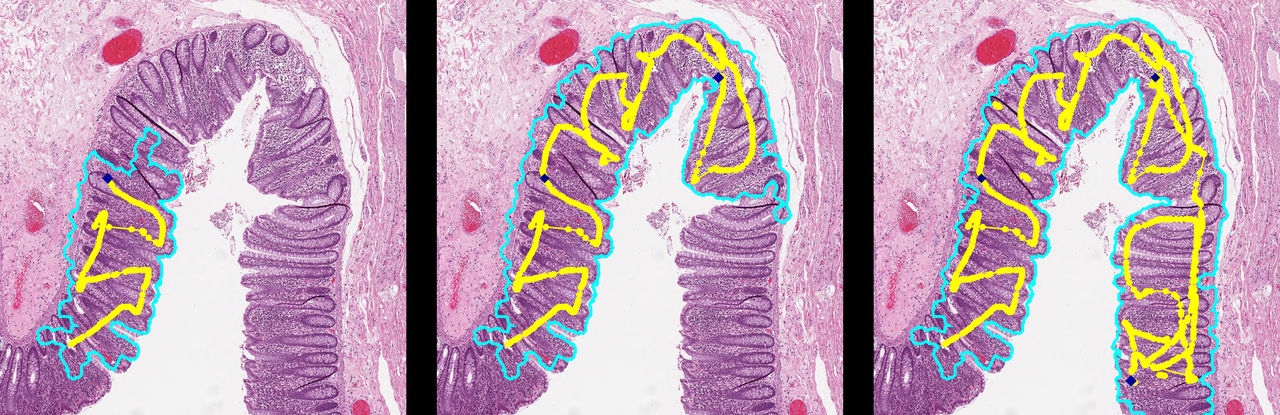

Utveckling av maskininlärning för komplex medicinsk bildanalys

Trots att maskininlärningsalgoritmer, särskilt de som nyttjar neurala nätverk, har visat på lovande resultat inom många medicinska bildanalysuppgifter (som segmentering, detektering och lokalisering) finns det ett antal utmaningar som måste lösas innan tekniken kan användas kliniskt.

Ett problem är robusthet i noggrannheten. En algoritm som tränats på sjukhus A kommer med största sannolikhet inte att fungera på data från sjukhus B. I många fall är bristen på exakthet så stor att algoritmen är obrukbar. För att uppnå resultat som kan generaliseras krävs mycket data från flera olika håll för inlärningen. Att få tillgång till tillförlitliga data av god kvalitet är här en utmaning.

Forskningens mål är att skapa större förståelse för de krav som behöver ställas på data för inlärning. Detta för att kunna styra inlärningen bättre, men också för att förbättra generaliserbarheten även utifrån en liten mängd data. Vi kommer att undersöka detta med hjälp av förstärkta data, simuleringar och generering av data med hjälp av nätverksbaserade system för inlärning - generative adversarial network, GAN - med mera.

Visualisering av hur HE-färgade vävnadsbilder skiljer sig när de härstammar från olika medicinska center. Bilden visar bilder från fem olika center, som idealt bör vara lika, men där de tydligt skiljer sig åt.